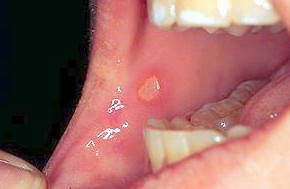

아구창이라는 것은 칸디다성 구내염을 말하는 것으로 한자로는 鵝口瘡(아구창)이라고 씁니다.

아구창은 칸디다 알비칸스라고 하는 곰팡이균에 의한 구강 감염입니다.

칸디다 알비칸스는 학명으로 Candida albicans라고 씁니다.